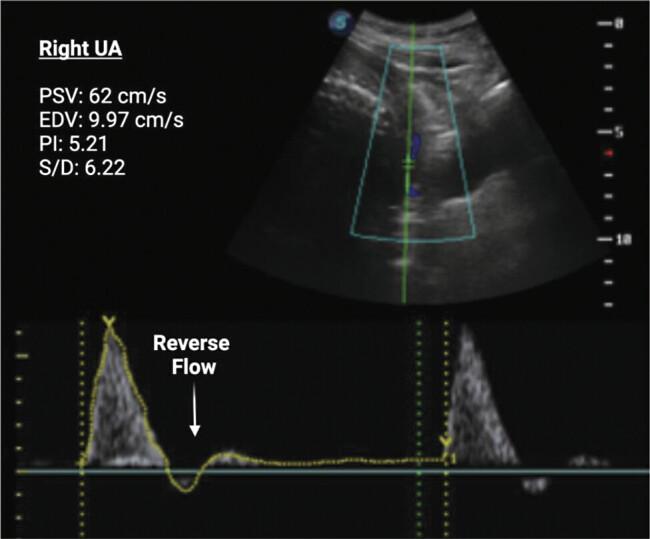

Preeclampsia is a multiorgan vascular disease complicating approximately 8.5 million pregnancies worldwide annually and is a leading cause of maternal and neonatal mortality. The impact is especially severe in Latin America, where maternal deaths attributable to preeclampsia are 2.5 times higher than in any other region. Bolivia is particularly affected due to economic and environmental challenges, including high altitude, which increases the risk of fetal growth restriction and hypertensive disorders of pregnancy. Early and accessible diagnostic tools are required to maximize patient care and improve reproductive outcomes in limited-resource settings. This report details a case from Bolivia of rapid-onset severe preeclampsia with liver rupture in the third trimester; the patient required multiple surgical interventions for recurrent liver bleeding and extended hospitalization in the intensive care unit (ICU). She delivered a preterm, growth-restricted infant with signs of acute hypoxia by emergency cesarean section. Notably, 2 weeks before ICU admission, abnormal uterine artery and maternal hemodynamic measurements were detected, without other signs of preeclampsia. The patient had previously been healthy and was considered low risk. Both mother and newborn survived. This case underscores the value of combining uterine artery Doppler with maternal hemodynamics to identify high-risk pregnancies early and prevent life-threatening complications.